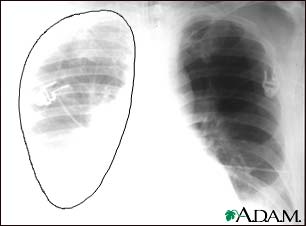

Tests that may be ordered include:

- Chest x-ray